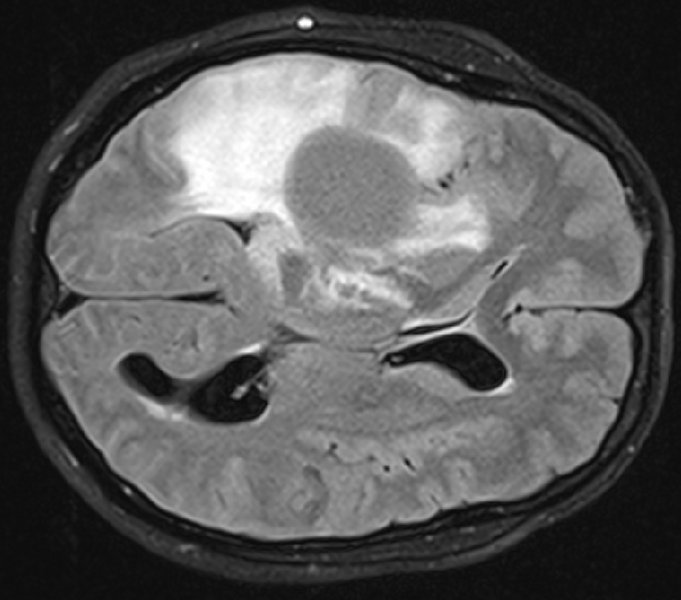

Diffuse Gliome sind meist unheilbare Hirntumoren, die sich im Gehirn ausbreiten und operativ nur schwer vollständig entfernt werden können. Auch Chemo- oder Strahlentherapie sind häufig nur begrenzt wirksam. Die diffusen Gliome haben vielfach eine besondere Gemeinsamkeit: In über 70 Prozent der Fälle tragen die Tumorzellen eine übereinstimmende Genmutation. Ein identischer Schreibfehler im Erbgut, der dazu führt, dass im Enzym IDH1* ein einziger, bestimmter Eiweißbaustein ausgetauscht wird. Dadurch entsteht eine neuartige Proteinstruktur – ein so genanntes Neoepitop, das vom Immunsystem des Patienten als fremd erkannt werden kann.

Bei einem großen Teil der Geimpften beobachteten die Ärzte eine so genannte „Pseudoprogression", ein Anschwellen des Tumors bedingt durch eine Armada einwandernder Immunzellen. Diese Patienten hatten besonders viele T-Helferzellen im Blut, deren Immunrezeptoren spezifisch auf das Impfpeptid reagierten, wie Einzelzell-Sequenzierungen ergaben. „Wir konnten außerdem nachweisen, dass die aktivierten mutationsspezifischen Immunzellen in das Hirntumorgewebe eingewandert sind", berichtet Theresa Bunse, DKFZ, die die immunologischen Analysen für diese Studien koordinierte.